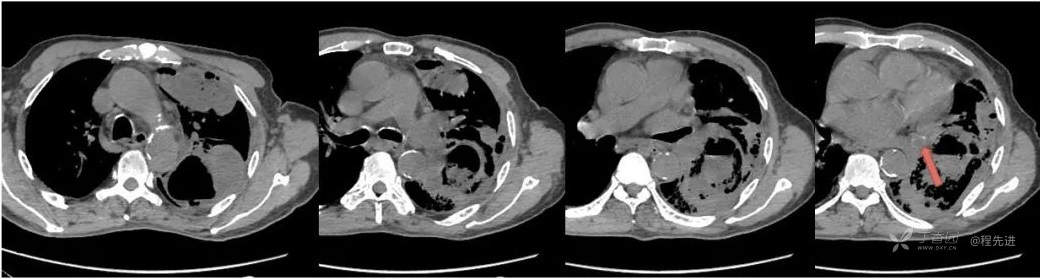

纵隔窗

2天后平扫+增强

肺窗

纵隔窗 红箭CT值33HU

增强红箭CT值70HU